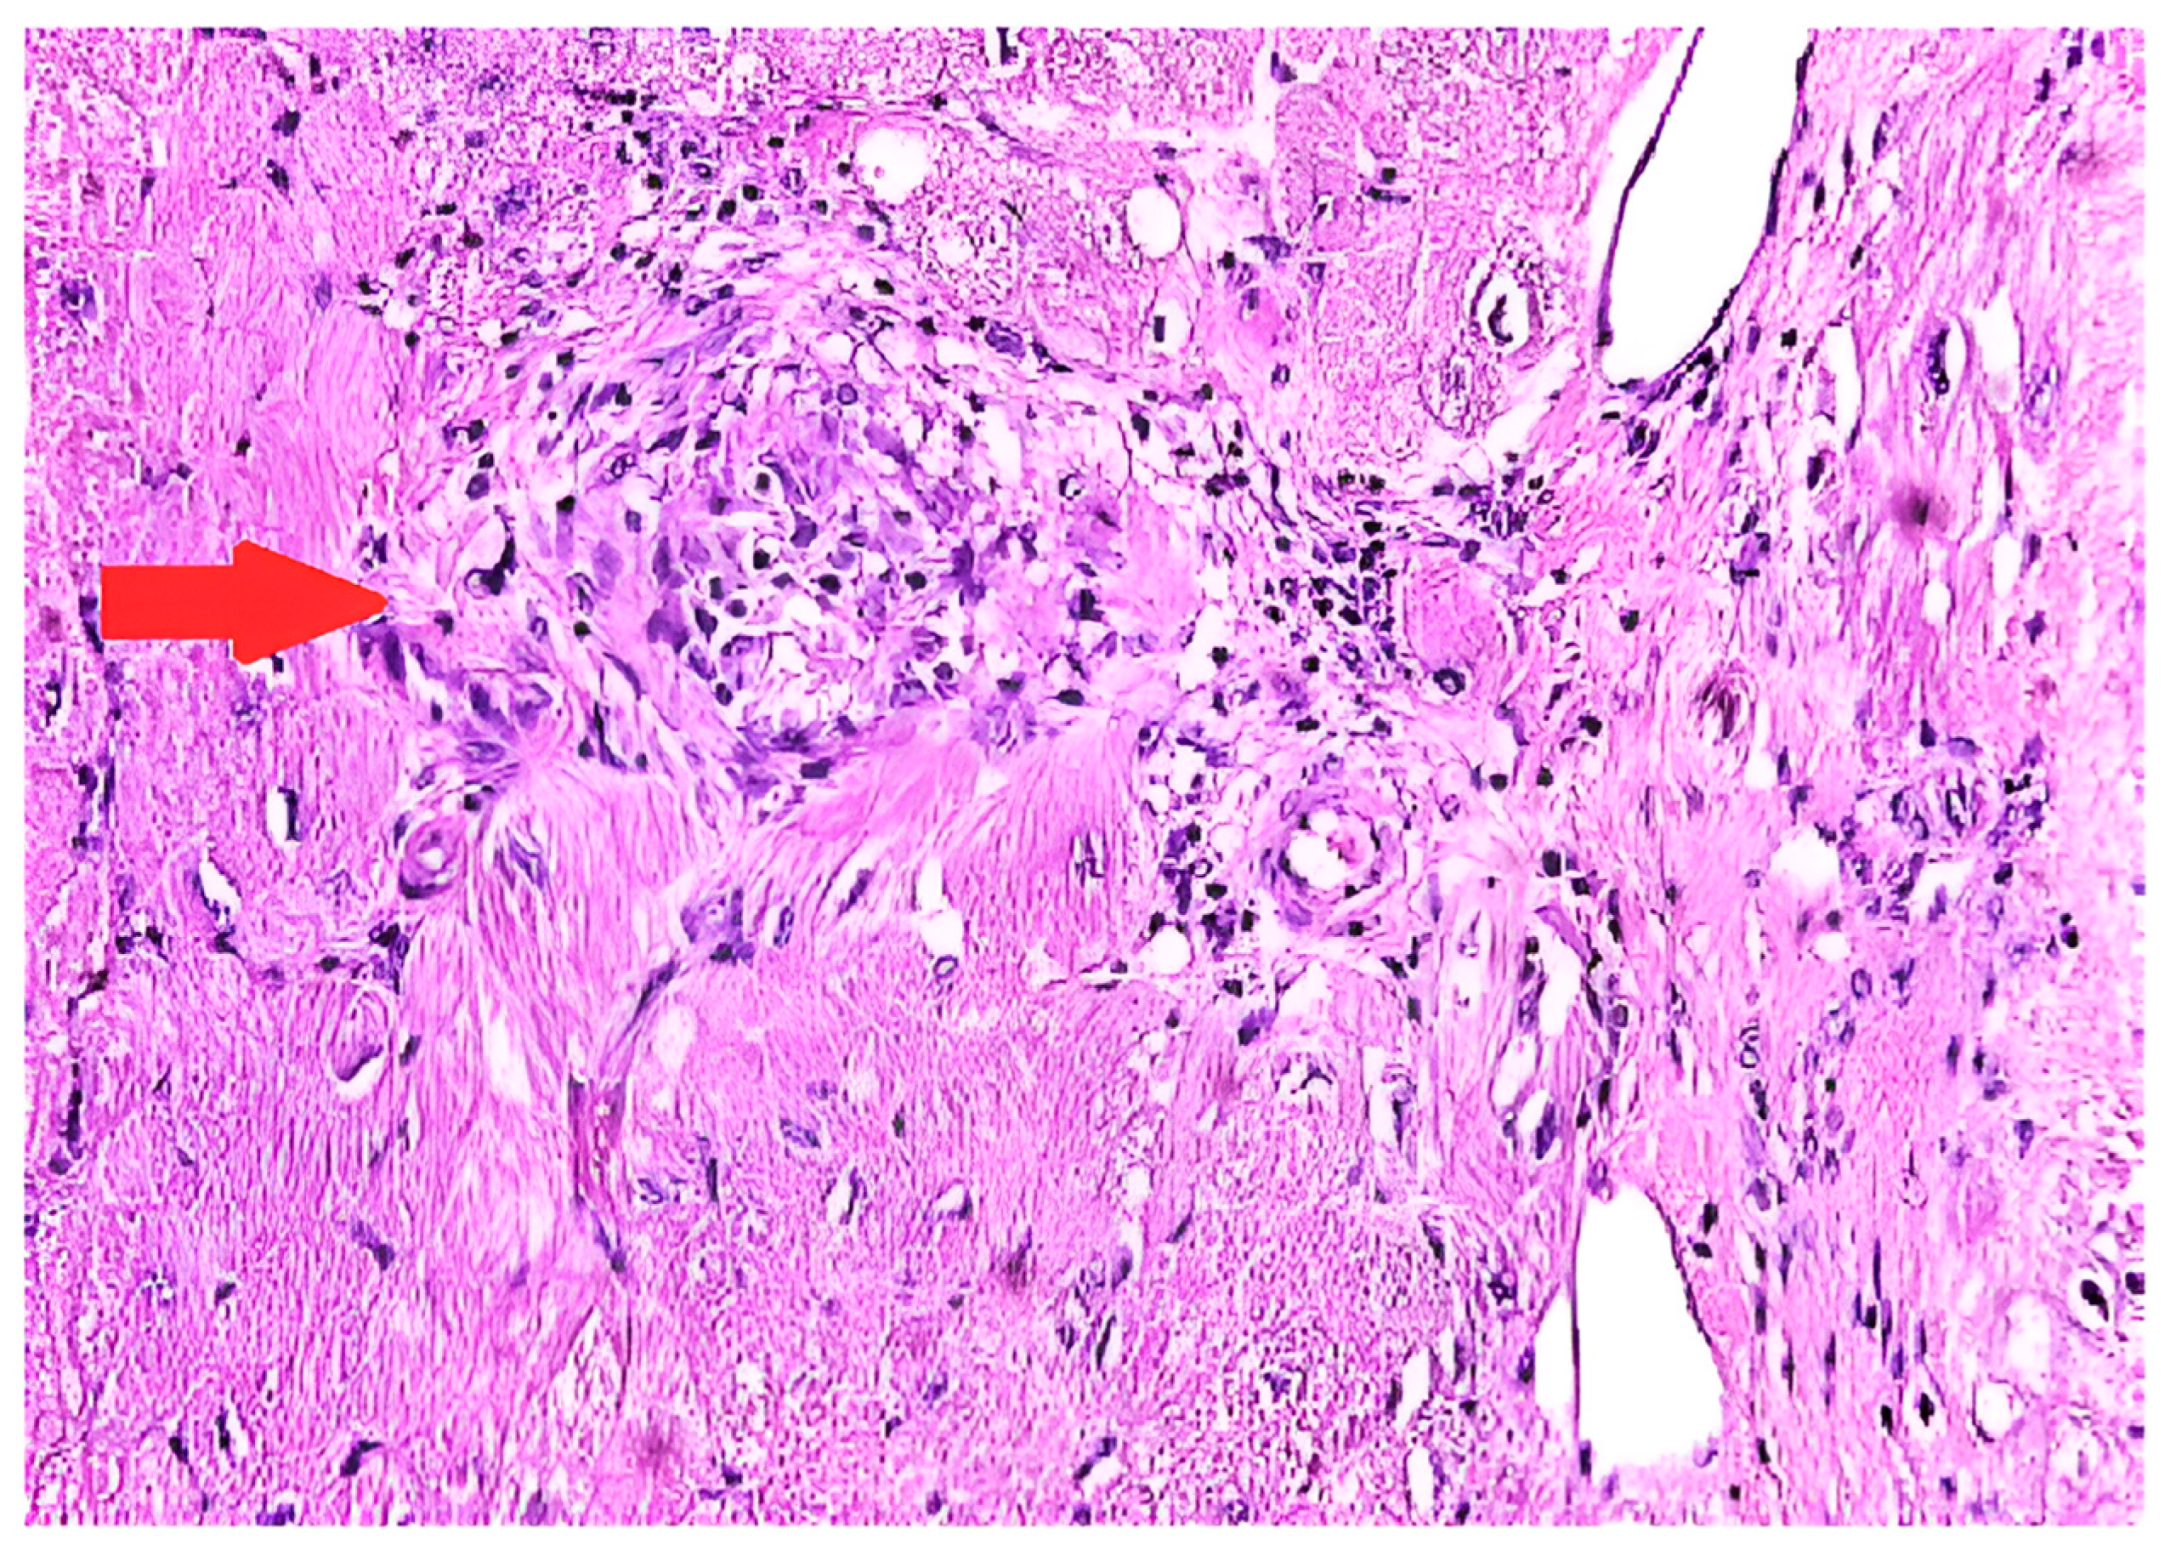

5.3. Endomyocardial Biopsy (EMB)